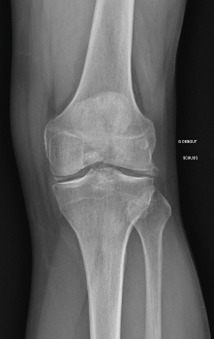

Les radiographies permettent de déceler des modifications ostéocartilagineuses asymétriques (mains, pieds, poignets, coudes, genoux), secondaires à la réaction inflammatoire autour des tophus, comportant :

• des érosions osseuses initiales caractéristiques : encoche épiphysaire (fig. 3) avec un éperon osseux (aspect en hallebarde) ;

• une image d’empreinte dans les parties molles (augmentation de la densité des parties molles dues au tophus) très évocatrice (fig. 4) ;

• un interligne longtemps conservé (contrairement aux autres rhumatismes destructeurs) [fig. 3] jusqu’au stade de goutte chronique et l’absence de raréfaction osseuse périarticulaire permettant de différencier la goutte d’autres arthropathies ; à un stade avancé, la goutte tophacée peut avoir un potentiel destructeur à la fois articulaire et osseux (fig. 4).

La forme pseudorhumatoïde est rare (5 %), simulant une polyarthrite rhumatoïde. L’arthrite chronique à PPC se présente comme une oligo- ou une polyarthrite, avec parfois des signes systémiques d’inflammation (élévation de la vitesse de sédimentation et de la protéine C-réactive [CRP]). La superposition d’accès aigus microcristallins est évocatrice de ce diagnostic. Il s’agit d’un diagnostic différentiel de polyarthrite rhumatoïde du sujet âgé ou de pseudopolyarthrite rhizomélique. Le diagnostic repose sur la mise en évidence des cristaux de PPC, même si les radiographies standard sont évocatrices. L’atteinte radiographique associe des calcifications des cartilages articulaires (fig. 7) et des fibrocartilages (fig. 8, 9, 10 et 11) [à rechercher systématiquement sur les radiographies de poignets, genoux et symphyse pubienne]. La mise en évidence d’une chondrocalcinose sur des radiographies standard renforce le diagnostic de rhumatisme à PPC mais l’absence de dépôts calciques ne l’élimine pas (la sensibilité de la radiographie standard étant imparfaite). L’échographie peut mettre en évidence des dépôts de PPC, qui apparaissent comme une fine bande hyperéchogène au sein des cartilages hyalins et comme des points scintillants dans les fibrocartilages ou dans la membrane synoviale. La sensibilité de l’échographie est bien supérieure à celle de la radiographie standard. Le scanner peut également mettre en évidence des dépôts calciques évocateurs, notamment au niveau du rachis ou du bassin qui sont plus difficilement explorés par les radiographies et l’échographie.